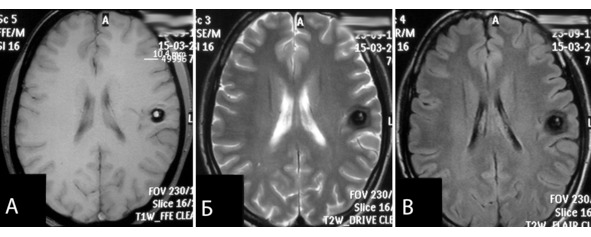

Возможности дооперационных методов обследования достаточно широки и к настоящему моменту позволяют поставить диагноз в подавляющем большинстве случаев. В 239 (79,1%) наблюдениях диагноз «кавернома» был очевиден до операции. В 63 наблюдениях (20,9%) не исключалась вероятность другой природы образования: опухоли (в подавляющем большинстве случаев, рисунок 16), гематомы вследствие разрыва микромальформации, тромбированной периферической аневризмы (в единичных случаях, рисунок 17). Наличие гипоинтенсивного кольца на МРТ в режимах T2 и FLAIR, обусловленного продуктами распада крови, является ключевым нейрорентгенологическим критерием для постановки диагноза «кавернома». Именно при его отсутствии возникают сомнения в дооперационном диагнозе и необходимость исключения опухолевой природы образования. На имеющемся материале доля каверном с этим признаком составляла 78,9%.

Рисунок 17. МРТ больной с каверномой латеральных отделов центральной борозды слева. Дифференциальный диагноз – кавернома или тромбированная аневризма. Патоморфологическое заключение – кавернома. А – режим Т1 в аксиальной проекции, Б – режим Т2 в аксиальной проекции, В – режим FLAIR в аксиальной проекции.